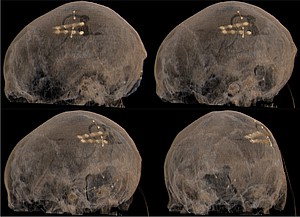

Motorkortexstimulation

Bei bestimmten Gesichtsschmerzen und Schmerzen nach Schlaganfällen kann durch das Einbringen von einer oder mehrerer Elektroden oberhalb der Gehirnoberfläche, die für die Bewegung des Körpers verantwortlich ist, eine Schmerzlinderung erreicht werden. Die Elektoden werden entweder auf oder unter die Nervenhaut gelegt. Das Gehirn selbst bleibt intakt, sodass die Stimulation auch wieder rückgängig gemacht werden kann.

Auch bei diesem Verfahren werden die Elektroden durch einen Impulsgeber angesteuert, der unter die Haut implantiert wird. Die abgegebenen elektrischen Impulse verändern die Schmerzwahrnehmung so, dass die Schmerzen weniger stark wahrgenommen werden. Die Einstellungen des Impulsgebers lassen sich von außen jederzeit verstellen, sodass die Stimulation an veränderte Bedürfnisse der Patient:innen stets angepasst werden kann.